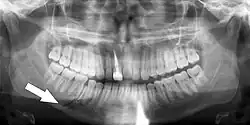

Panoramic radiograph of a simple mandible fracture of the right mandibular body, minimally displaced. Note that the teeth to the left of the fracture do not touch -

Panoramic radiography

Panoramic radiographs are tomograms where the mandible is in the focal trough and show a flat image of the mandible. Because the curve of the mandible appears in a 2-dimensional image, fractures are easier to spot leading to an accuracy similar to CT except in the condyle region. In addition, broken, missing or malaligned teeth can often be appreciated on a panoramic image which is frequently lost in plain films. Medial/lateral displacement of the fracture segments and especially the condyle are difficult to gauge so the view is sometimes augmented with plain film radiography or computed tomography for more complex mandible fractures.